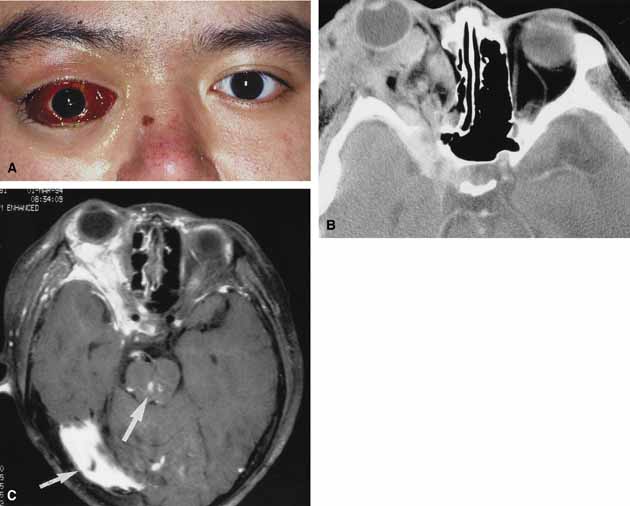

No-flow malformations (so-called lymphangiomas) have nonfunctional vascular systems that arborize through variable portions of the orbit.73 They may appear as superficial, deep, combined, or complex lesions.74 Clinically they are characterized by syndromes consisting of episodes of acute exacerbation and remission, often related to an upper respiratory tract infection. Although they are hemodynamically isolated from the systemic circulation, nutrient vessels within their fragile walls may be the source of sudden hemorrhage into their lumens, which transforms microscopic channels and cysts into blood-filled macrocysts (so-called chocolate cysts). Hemorrhage within a retrobulbar lesion may be dramatic, causing sudden proptosis (Fig. 8A and 8B). The patient has pain, decreased ocular motility, and decreased vision. Involvement of superficial components will lead to disfigurement of the lid, as well as swelling and ecchymosis of the conjunctiva. Management is similar to other orbital hemorrhages with canthotomy, cantholysis, and/or orbital decompression. Surgical decompression if required is aimed at evacuating the blood-filled cysts. Combined and complex lesions are frequently massive in size involving the intraconal, extraconal, preseptal, and postseptal spaces (Fig. 9A and 9B).75,76 They produce significant cosmetic disfigurement and may extend beyond the confines of the orbit into the intracranial space. In addition, isolated intracranial vascular anomalies may be noted (Fig. 9C). These combined lesions often require orbital surgery either on an acute basis, when there is an acute retrobulbar hemorrhage with optic nerve compression, or on an elective basis to deal with cosmetic disfigurement or chronic compression. Such surgery must be approached cautiously because of the risk of iatrogenic hemorrhage. Oral or intravenous steroids are also beneficial in the treatment of acute flare-ups.

Fig. 9 A. A 20-year-old male with extensive right facial and orbital lymphangioma presented acutely with proptosis, subconjunctival hemorrhage, double vision, and orbital pain. B. Axial computed tomography (CT) scan reveals extensive involvement of the orbit. The abnormal tissue also extends through the superior orbital fissure to the cavernous sinus area. C. Magnetic resonance imaging (MRI) scan reveals not only the extensive orbital involvement but also vascular anomalies in the midbrain and cerebellum (arrows).